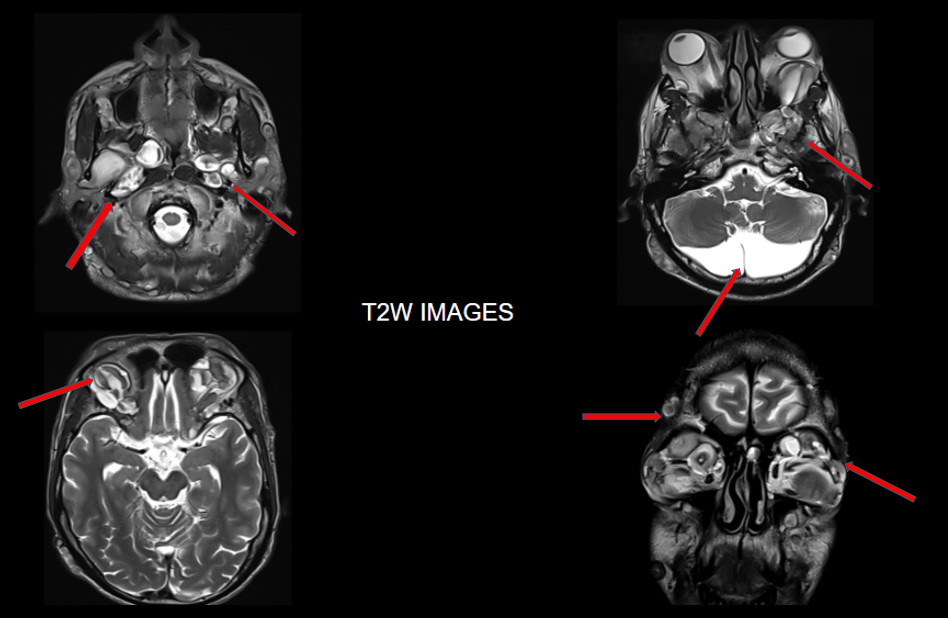

Multinodular T2 hyperintense hypointense transpatial lesions seen within the bilateral orbits occupying the intra and extraconal spaces with targetoid appearance.

The lesion extends through the inferior orbital fissure into the pterygopalatine fossa bilaterally.

The lesions also extend through the foramen ovale into the superior aspect of masticator space bilaterally.

Similar heterogeneously enhancing nodular lesions are also seen bilateral fronto-temporal and occipital scalp regions. Incidental retrocerebellar arachnoid cyst.

Lesion extends into the orbital apex and along the bilateral cavernous sinuses.

Similar heterogeneously enhancing nodular lesions are seen extending into the upper neck in bilateral parotid and the visualised level II regions.

They are best visualised on fat suppressed T2 weighted MR imaging where they appear as hyperintense masses with or without multiple target signs.